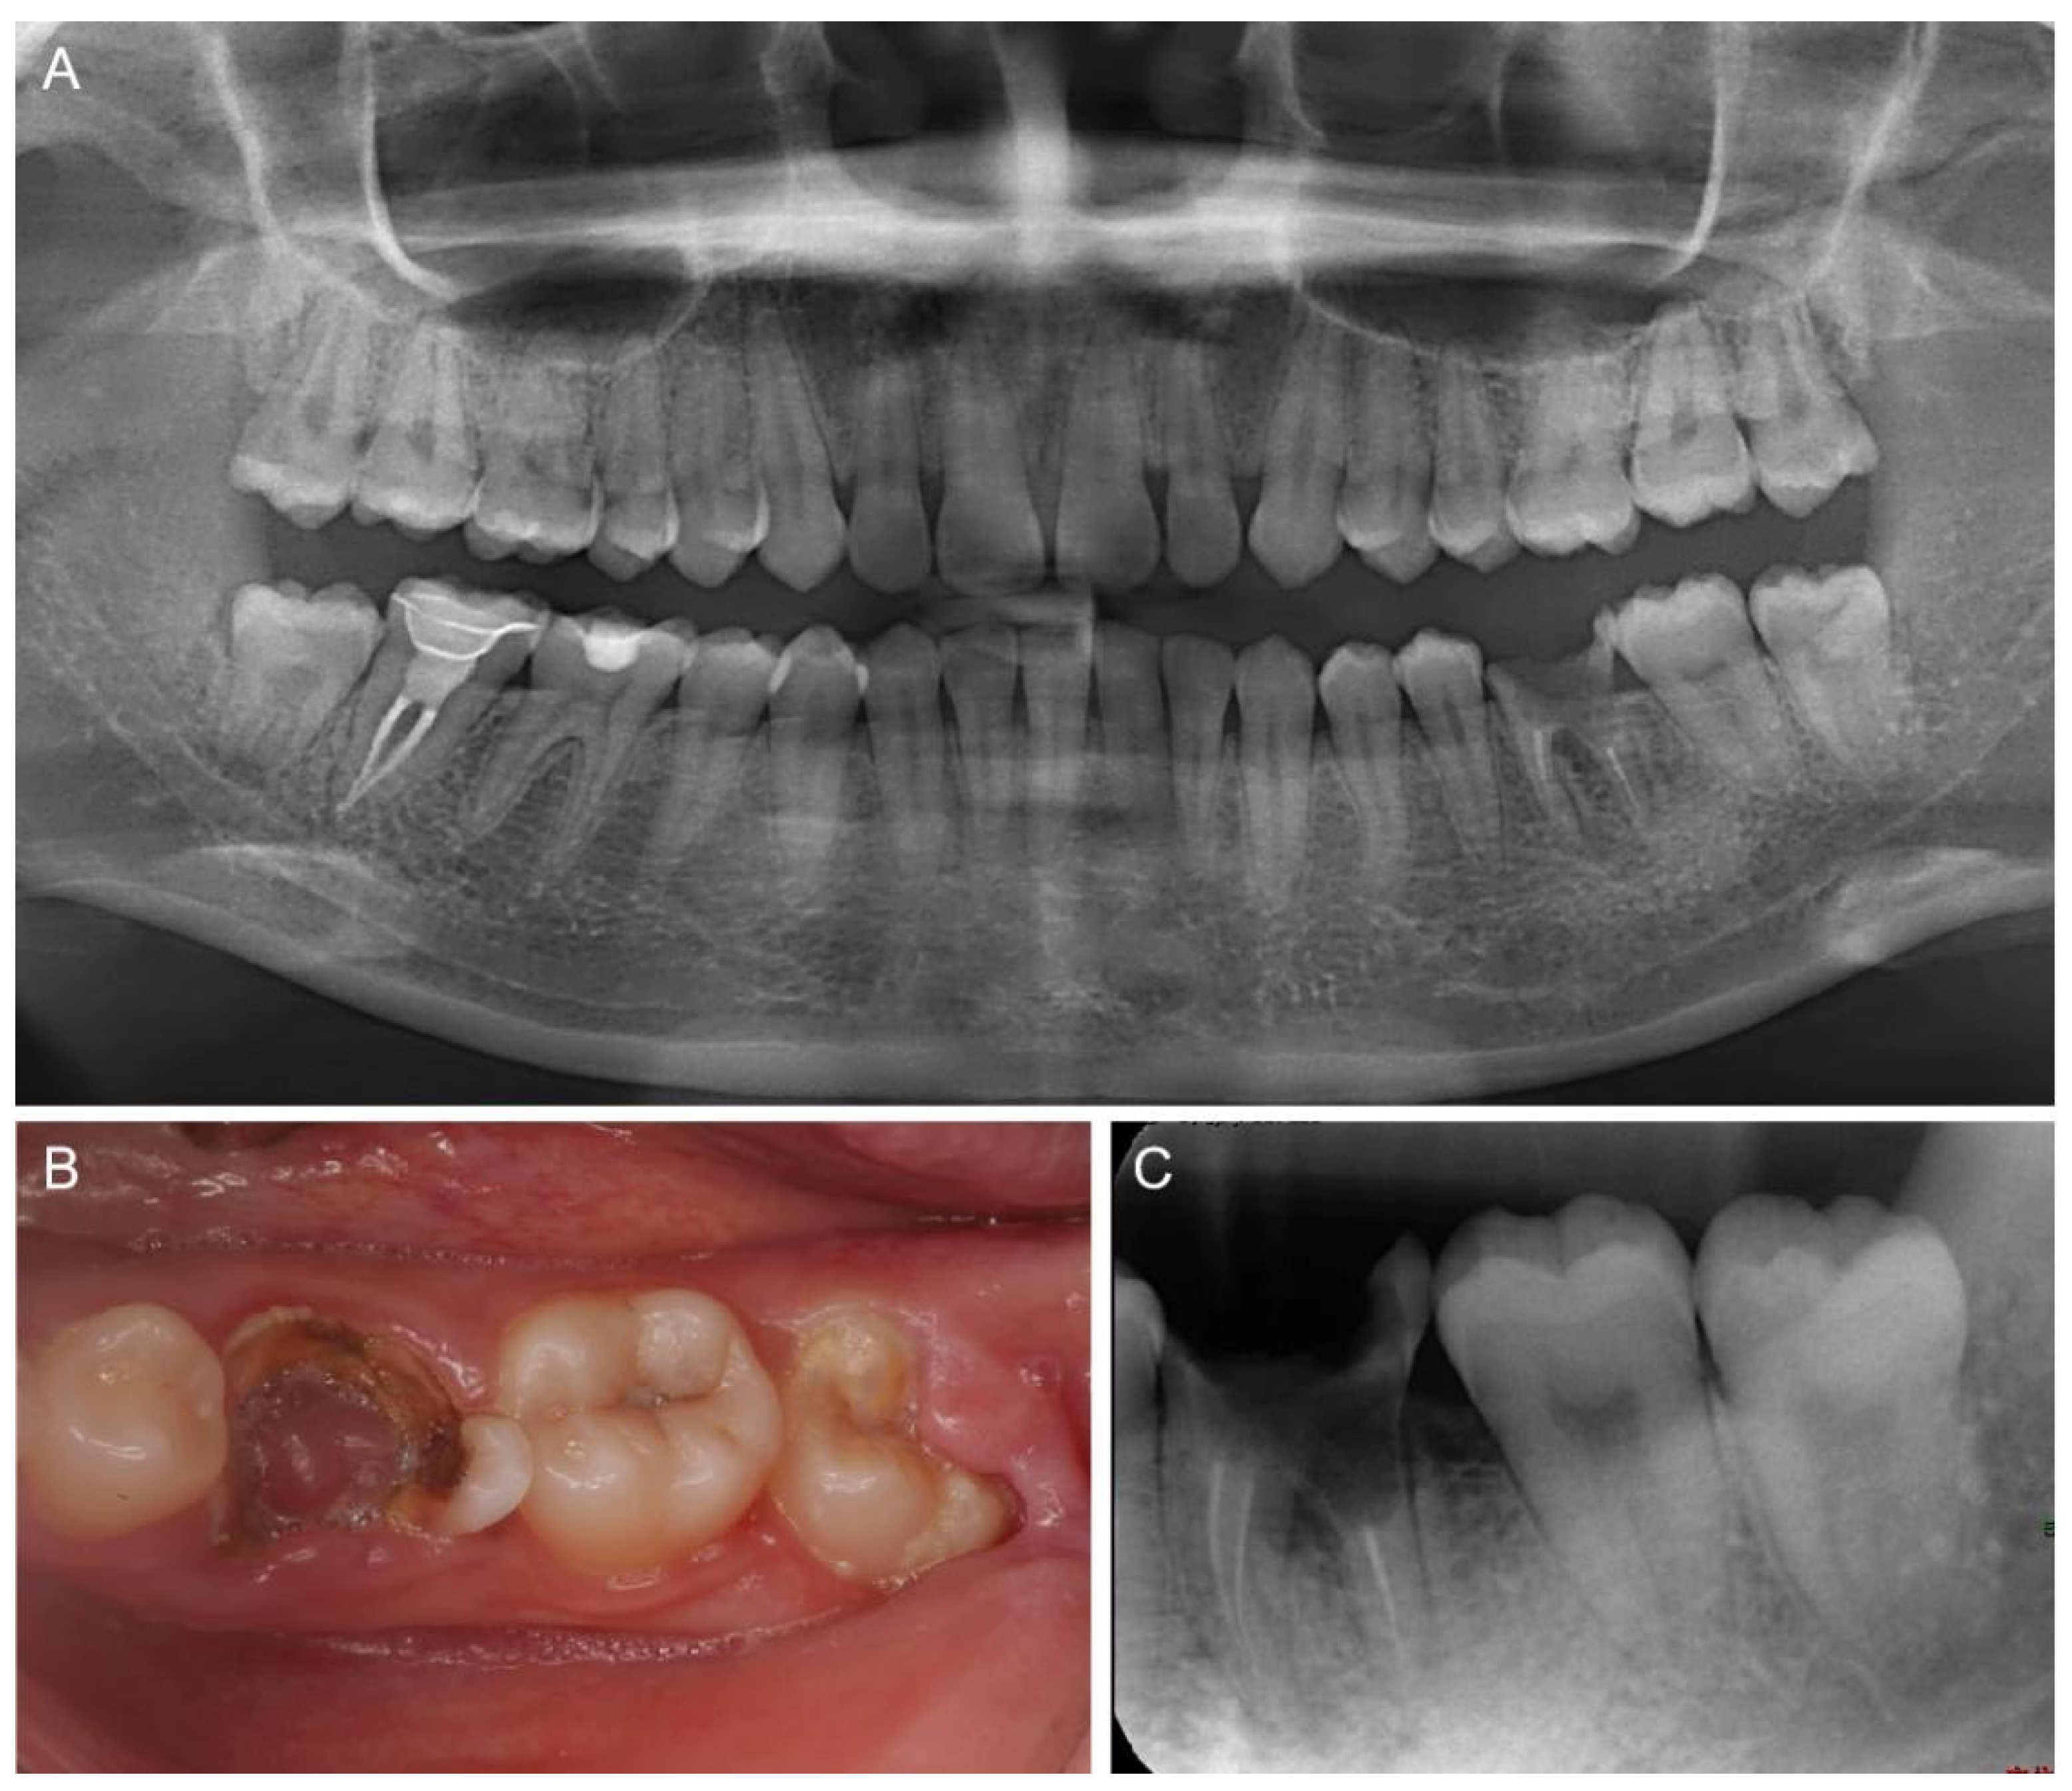

2. Case Report

2.1. Clinical Examination and Treatment Planning